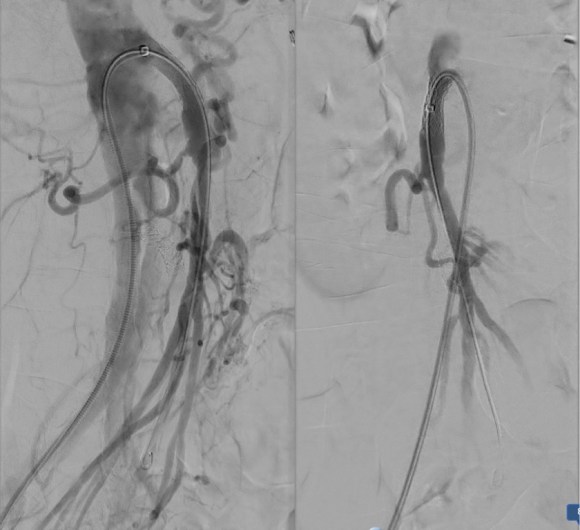

The patient thought this was reasonable and agreed. She underwent a midline laparotomy and I exposed both the SMA and right common iliac artery in the retroperitoneum and tunneled a PTFE graft in a C-pattern in the retroperitoneum. The SMA was diseased proximally under the pancreas and affected by inflammatory scar tissue, and the vessel was thickened as well. The iliac pulse was normal and full and provided excellent inflow.

The recovery was notable for remission of her chest pain and her ability to resume eating without pain or nausea. A CTA done before discharge showed a patent bypass.